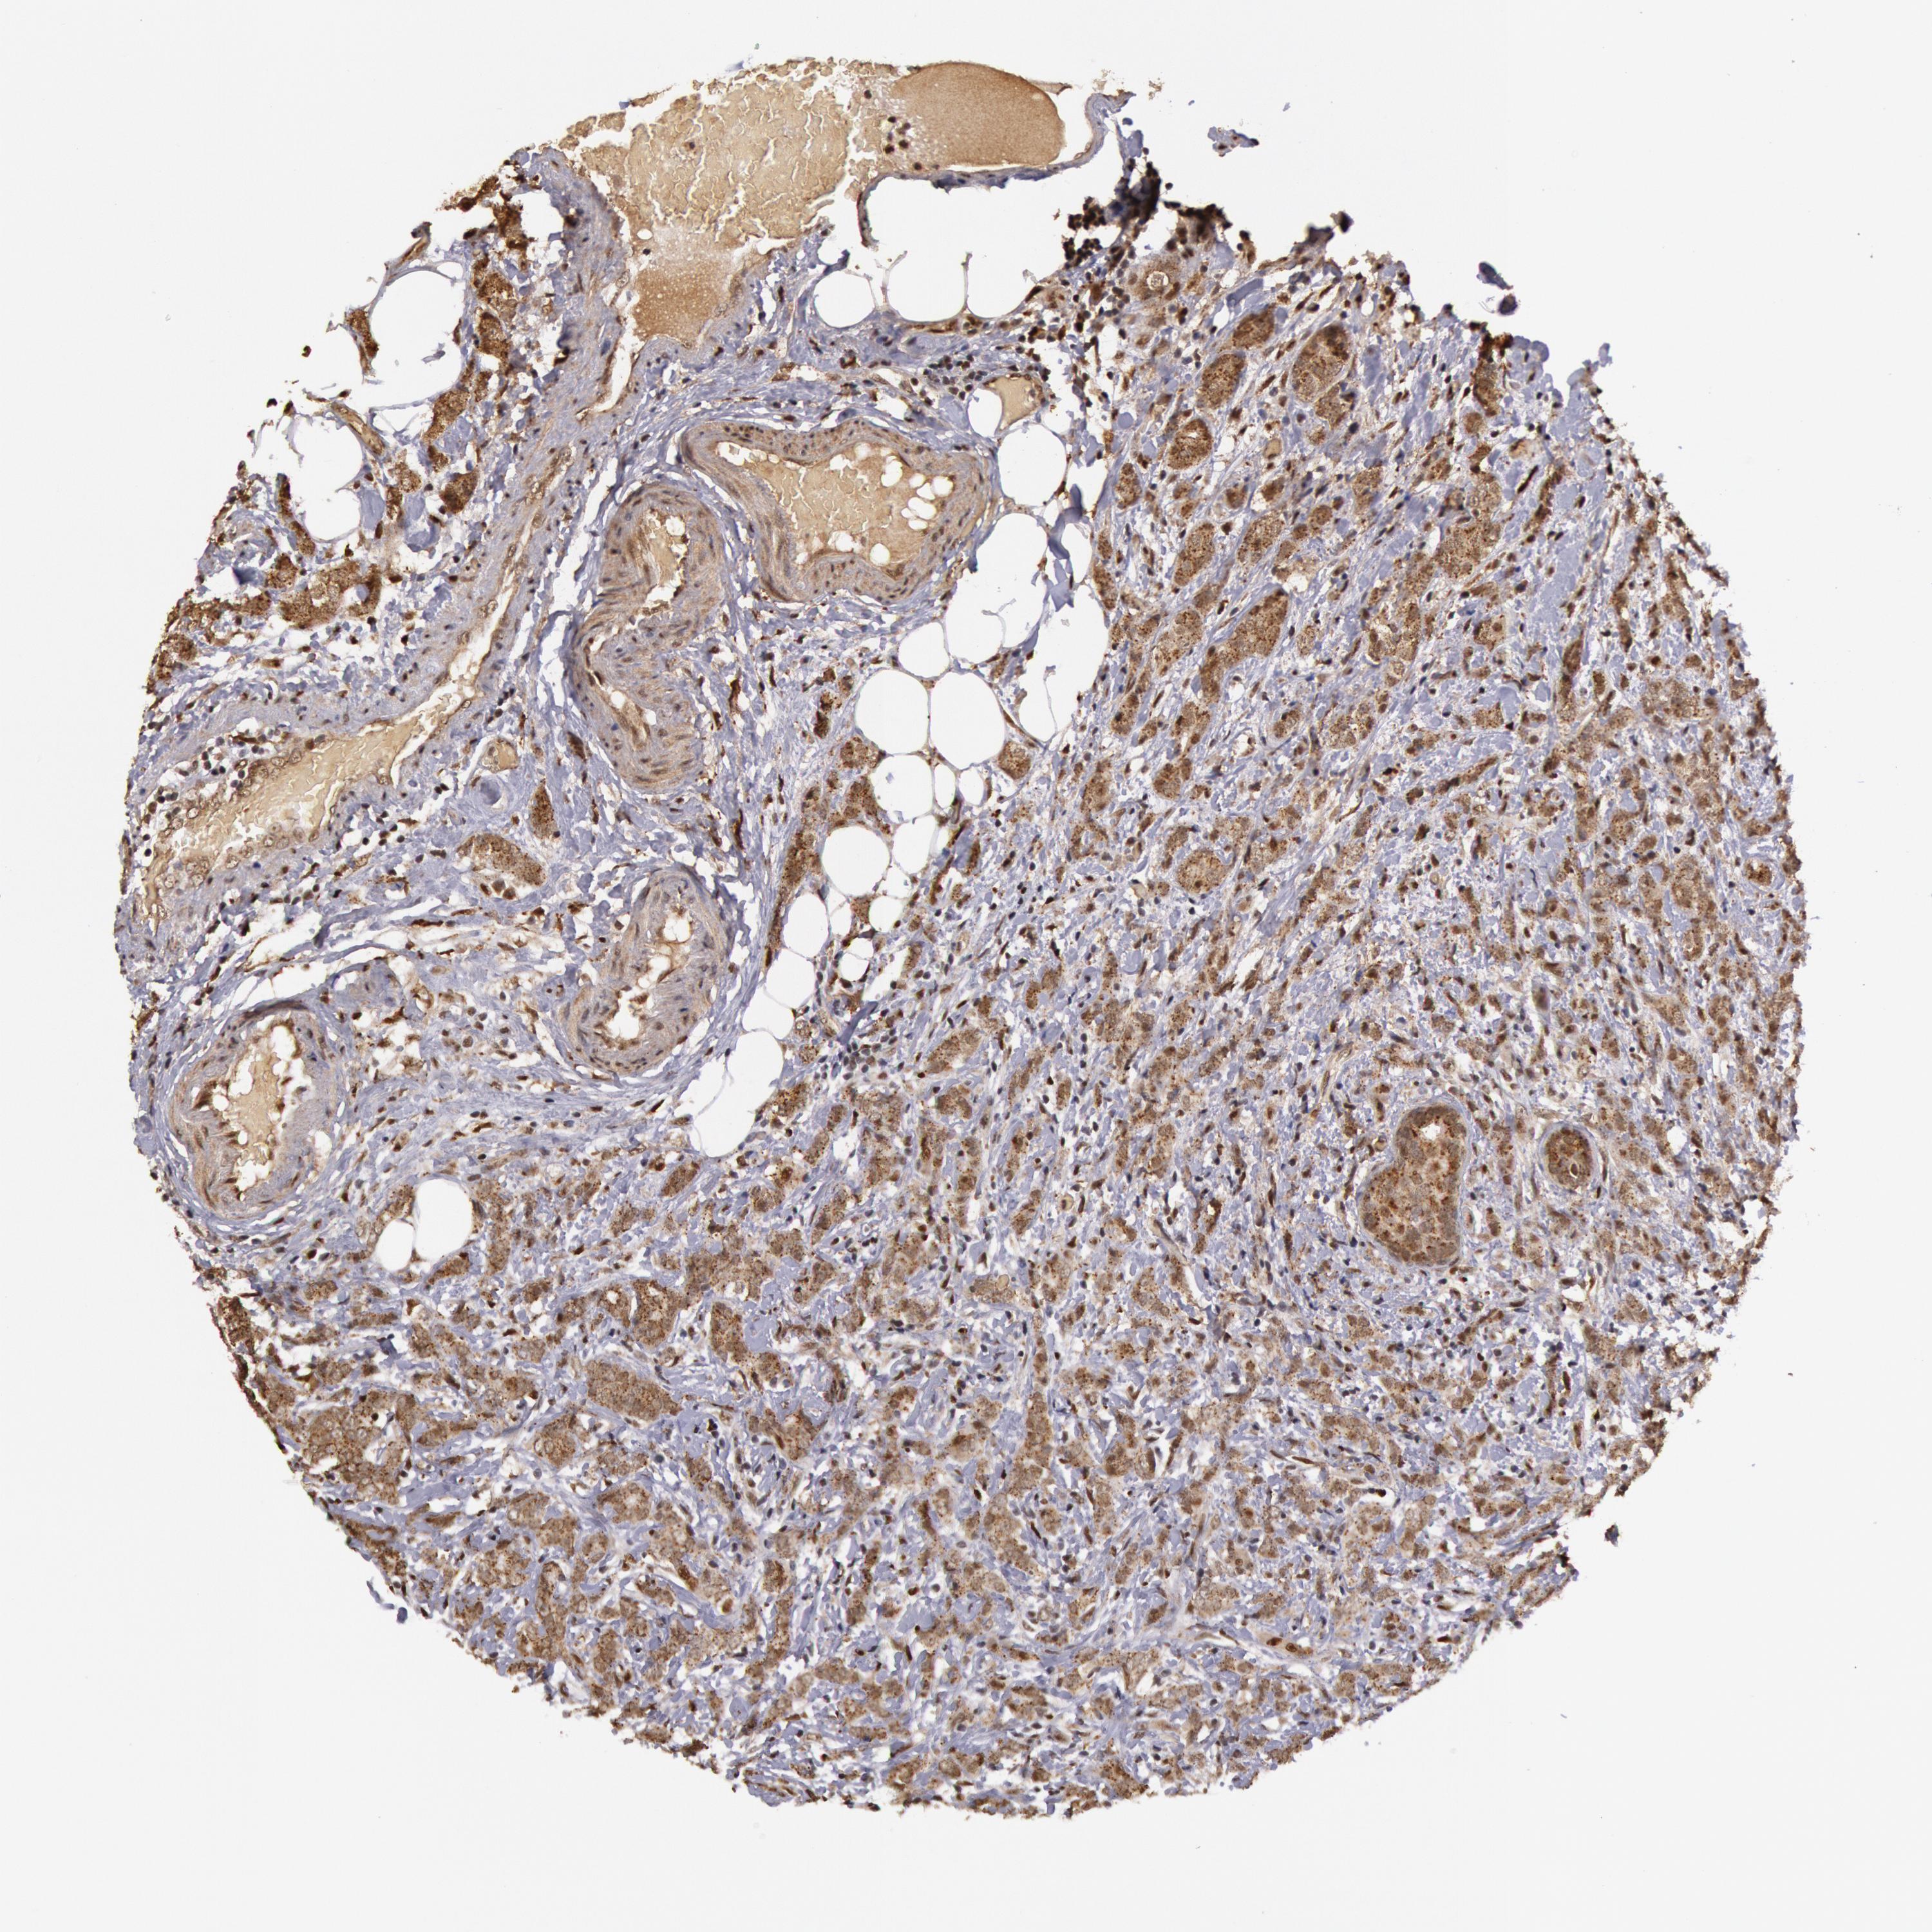

CANCER BREAST CANCER Show tissue menu

BRCA TCGA BRCA VALIDATION PROTEIN EXPRESSION